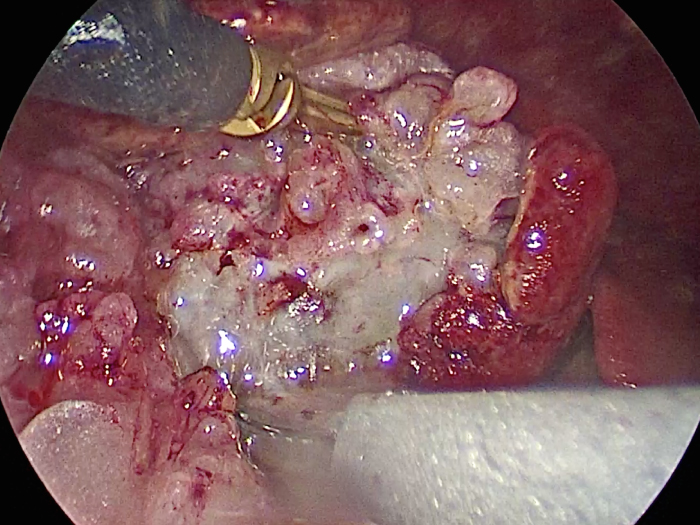

摘出した胆嚢はカチカチで中にはゼリー状の硬い物質が詰まっていました。

体の外に出すためお腹の中で袋に入れていきます。

このときに胆嚢と一緒にクリップやガーゼも回収します。

そしてお腹の中をきれいにしていきます。

最後にお腹の中をきれいに洗浄していきます。